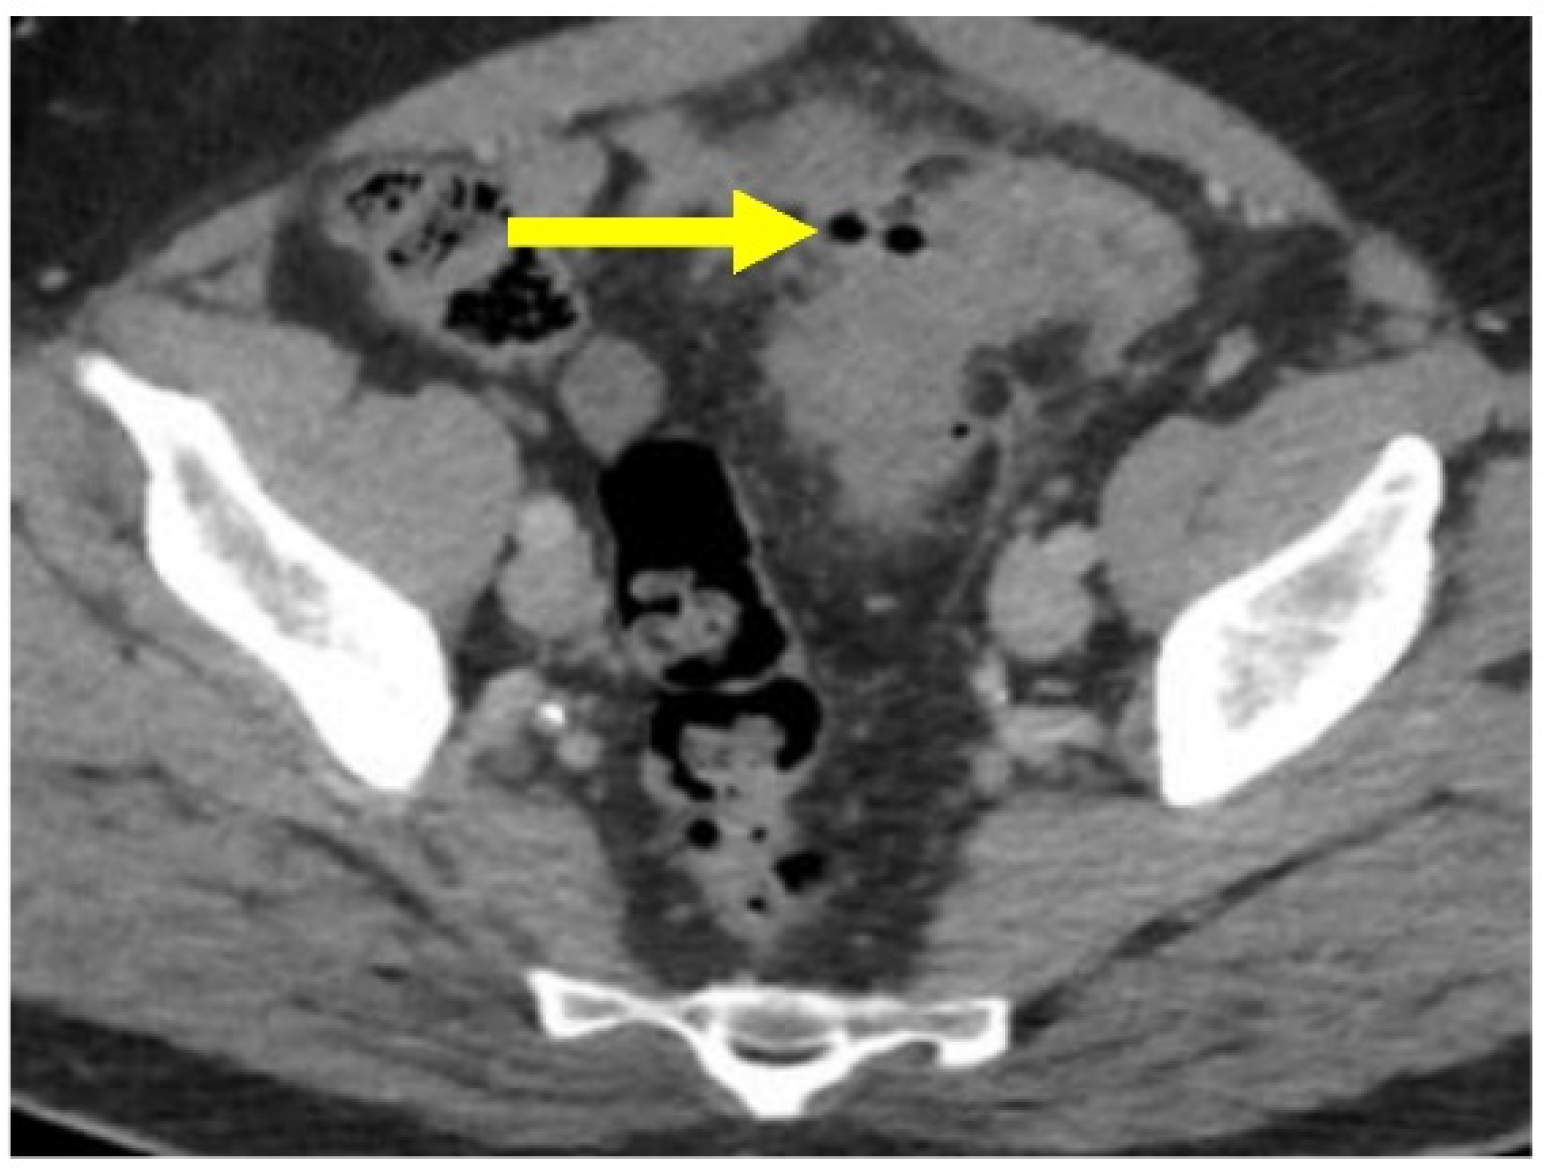

- Minordi, L.M.; Larosa, L.; Berte, G.; Pecere, S.; Manfredi, R. CT of the acute colonic diverticulitis: A pictorial essay. Diagn. Interv. Radiol. 2020, 26, 546–551. [Google Scholar] [CrossRef] [PubMed]